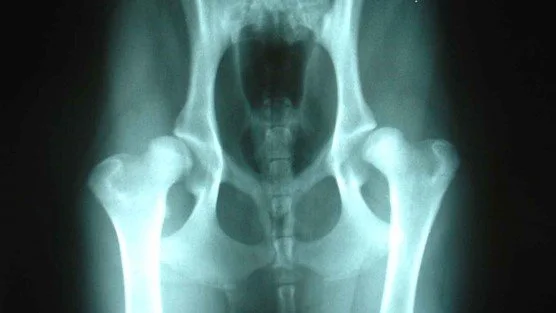

X-rays under an anaesthetic is essential. This allows us to manipulate the joints without causing any pain to our pets and thus get a really good image of the joint. There are several areas we examine on the X-ray shown in the picture.